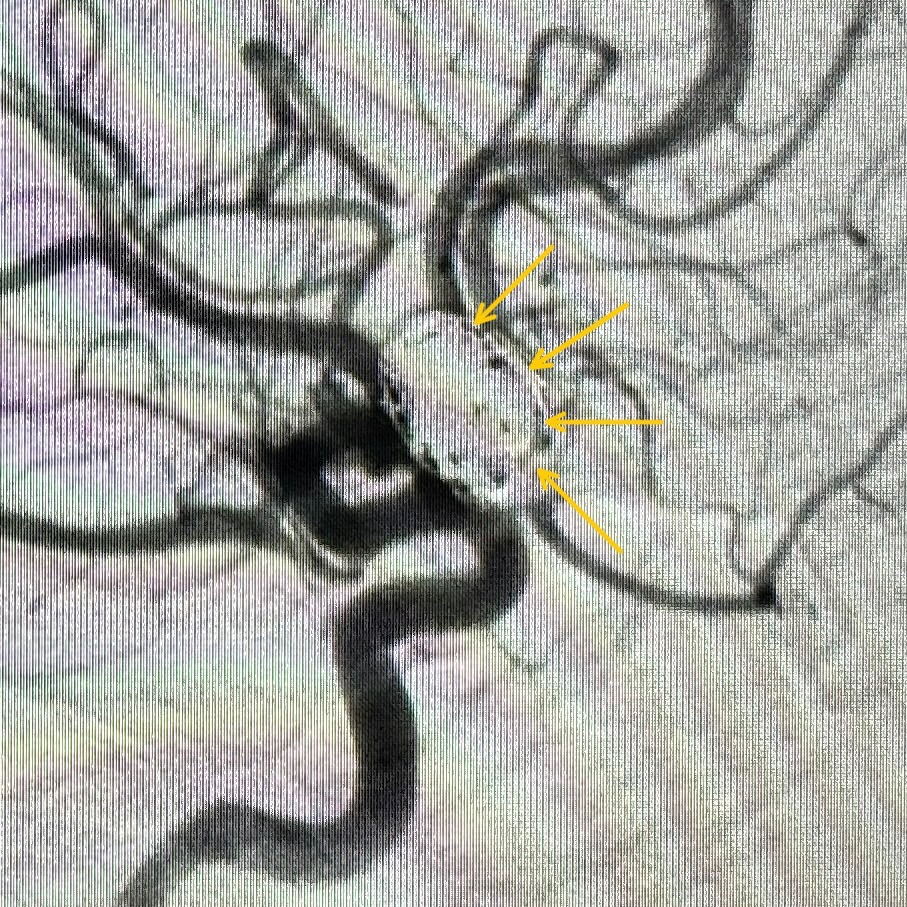

رجعنا دخلنا ملفات حلزونية إضافية لحد ما قفلنا كل جزء من التمدد. وفي الصورة التانية، الأسهم الصفراء 🟡 بتبيّن إن التمدد بالكامل بقى مقفول بإحكام.